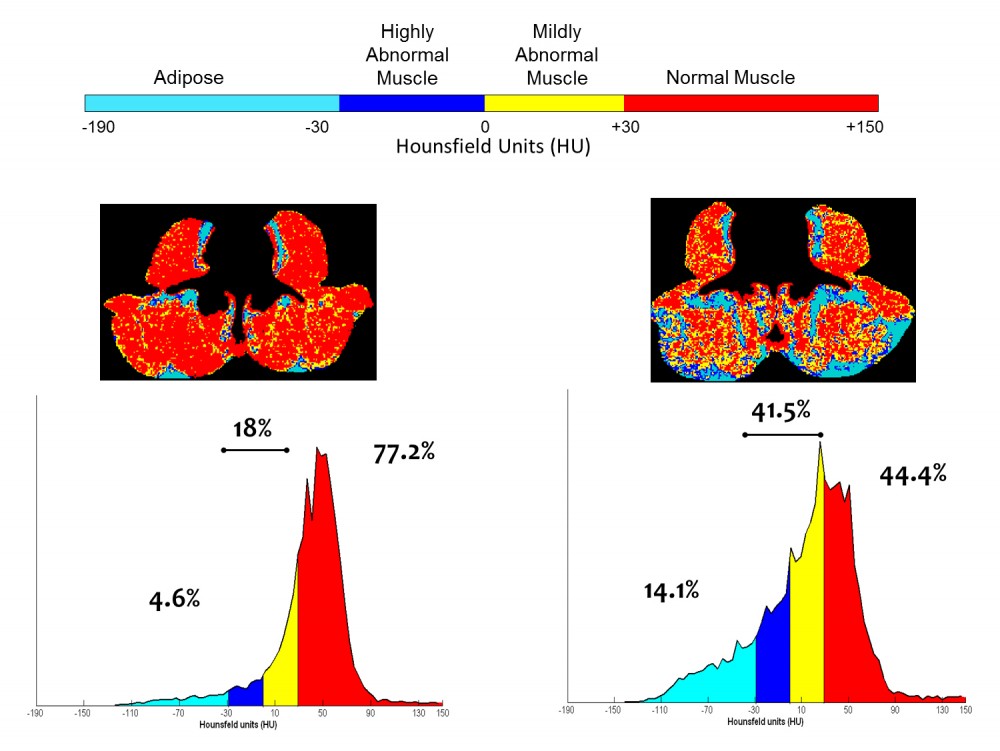

Fig. 2: This slide shows a CT image from a cancer patient who underwent 16 weeks of first line platinum doublet chemotherapy for lung cancer. Only the intramuscular adipose tissue is shown in colour.

Fig. 3: An illustration of annotated CT images, and accompanying histograms of radiation attenuation showing the percentages of total tissue cross-sectional area within the ranges of adipose tissue in paraspinal/psoas muscles is useful to understand the problem of myosteatosis. This illustration shows the percentages of total tissue cross-sectional area within the typical attenuation ranges determined for the respective tissues for 2 subjects. Subject 1 is a 63 year old male with muscle characteristics at the median values for male cancer patients with a diagnosis of solid tumour at our centre. For Subject 2 there is extensive macroscopic adipose tissue and less than half of the cross sectional area of his muscles falls within the normal attenuation range. Overall, Patient I has a greater proportion of fat and low attenuation muscle, than muscle with normal characteristics. Patient II is remarkable in several respects, including extensive visible fatty infiltration and extremely high proportion of total muscle area falling within a range of attenuation values generally recognized to be abnormally low (adapted from Aubrey et al 2014).